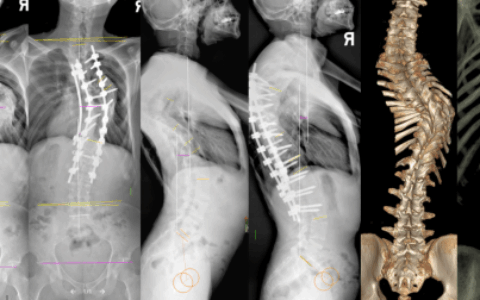

影像检查发现,患者腹腔中盘踞着一个20.6cm、形似哈密瓜大小的肿瘤,左侧腹盆腔、腹膜后、右侧腹壁等部位也发现多个肿瘤,这些肿瘤不仅像“藤蔓”般吸附包裹在左肾及腰大肌上,更将肠管、胃、肝脏、胰腺、脾脏等邻近脏器挤压得移位变形。

海南省肿瘤医院、海南成美医院院长、知名胃肠外科专家余书勇教授和胃肠外科一病区副主任蔡耀庆等进一步检查评估发现,肿瘤不仅体积巨大,侵犯多个脏器,且位置较深,紧贴着腹主动脉、下腔静脉等大血管。

蔡耀庆介绍,术中探查时发现,情况比预想更加糟糕,巨大的瘤体几乎塞满了整个盆腹腔,网膜和腹盆腔里还散布着大大小小近20个肿瘤病灶,与横结肠、胃、左肾、脾脏、胰腺形成了致密粘连,俨然构成一个复杂的“肿瘤卫星城”。